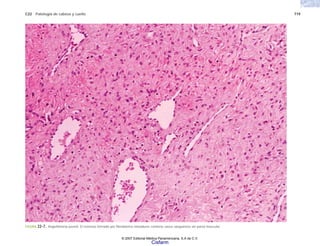

FIGURA 6-13. Granuloma tuberculoso con necrosis central rodeada de células epiteloides en empalizada y células gigantes multinucleadas.